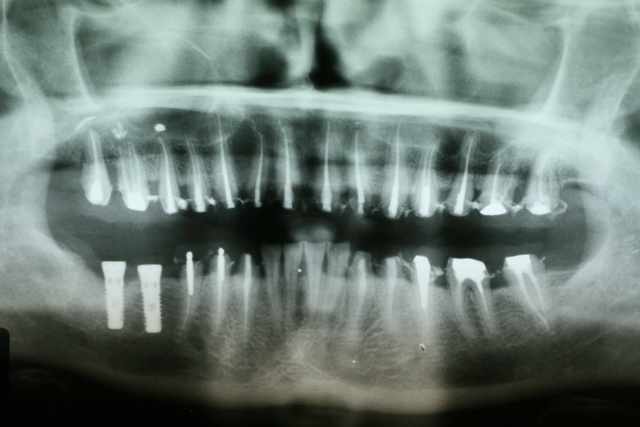

pano avec inlays cores .

bridge pro scellé en provisoire c'est mon "laboratoire d'essai" ce qui va valider la dvo pendant toute la phase de cicatrisation et d'adaptation occlusale...

jamais de descellement ....

cette pano est en date du mois de 05/2006

j'ai donc fait patienter pendant 11 mois sous provisoires pour valider la DVO et l'occlusion si le compte est bon

Pano 13052006 dcktdn - Eugenol